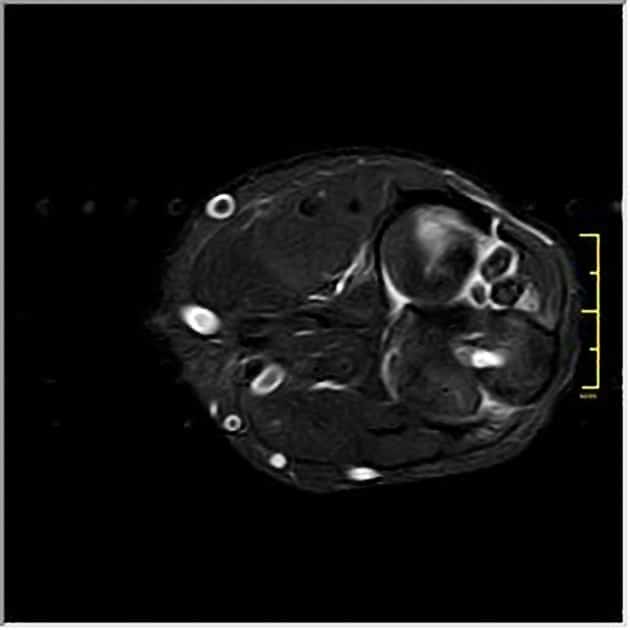

U sụn màng hoạt dịch

» Thông tin: Nữ giới – 32 tuổi.

» Lâm sàng: Đau khuỷu tay 2 năm.